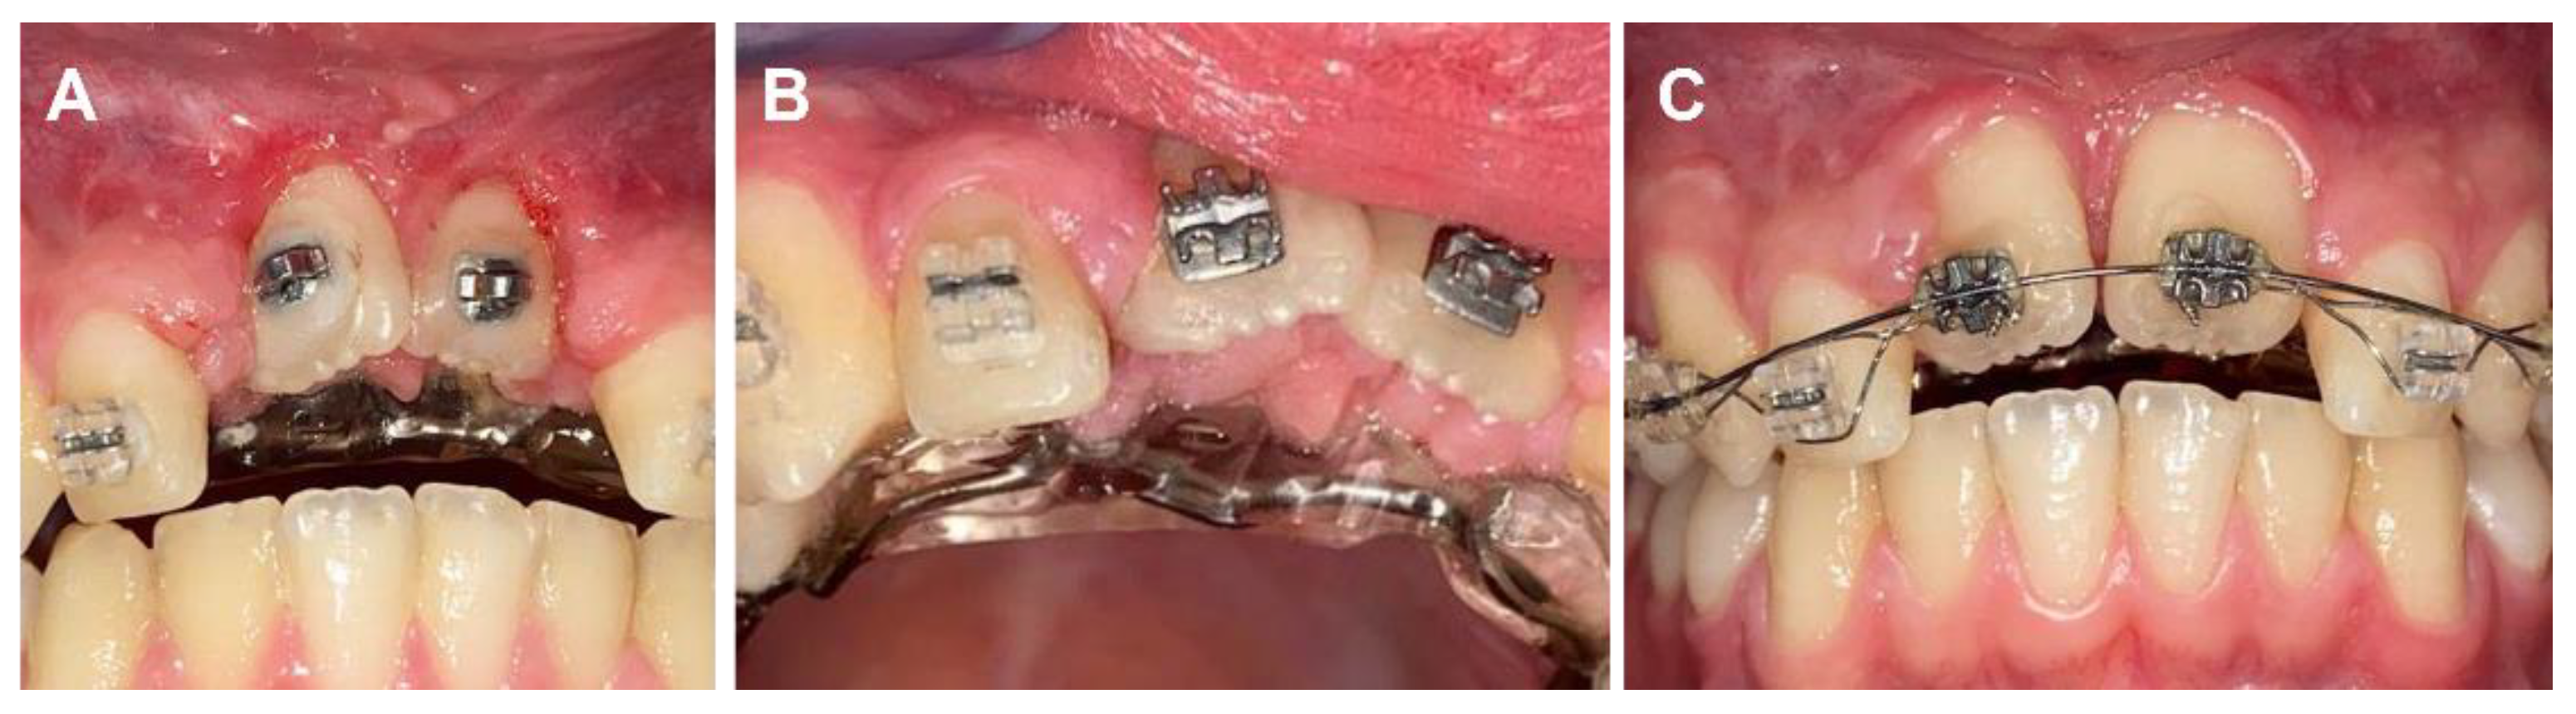

2. Case Report

2.1. Clinical History

2.2. Clinical Exams and Diagnosis

2.3. Therapeutic Plan